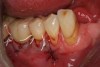

The entry of inflammatory cell infiltrate into the connective tissue (Figure 1 and Figure 2) differentiates peri-implantitis from peri-implant mucositis.1 Unlike a natural tooth—where periodontal fibers, transepithelial fibers, and gingival fibers absorb this exudate—none of these fibers are present around an implant (Figure 3). This allows the inflammatory cell exudate to directly enter the bone, resulting in bone loss and concomitant soft-tissue loss (Figure 4).1

Fig 2. Inflammatory cell exudate enters right into the bone.

Figure 2